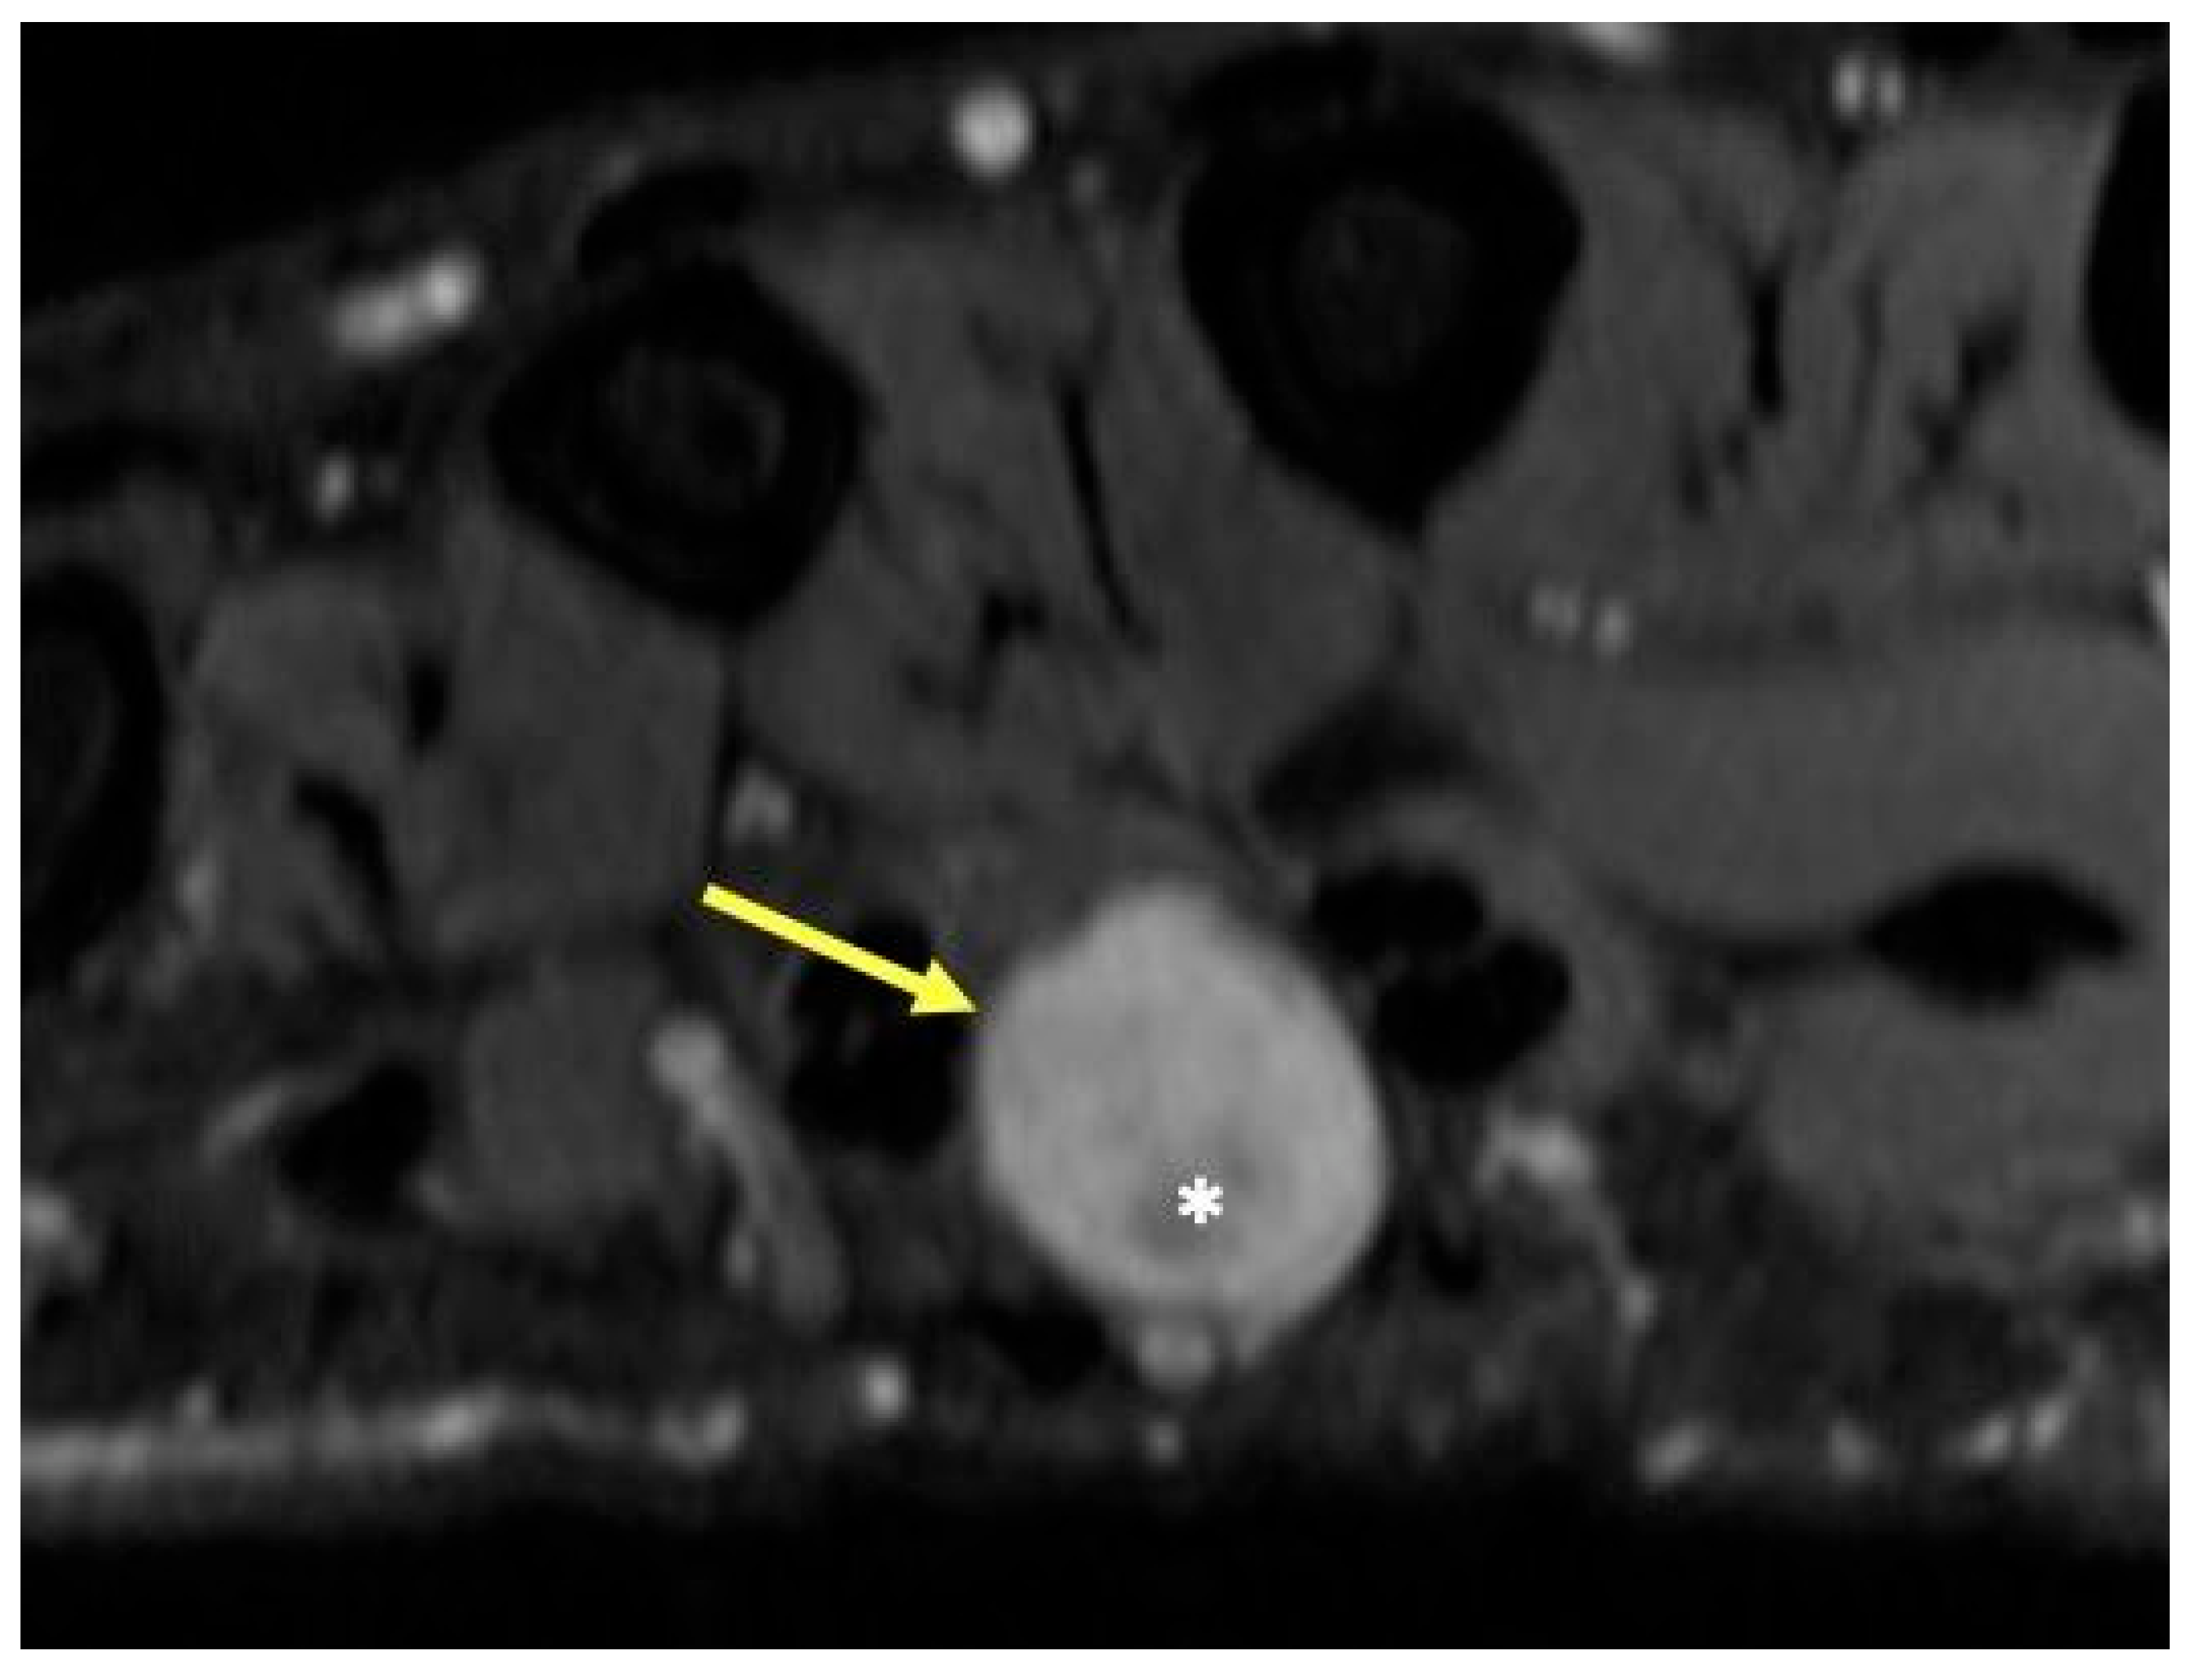

2.10. Foreign Bodies of the Hand

2.10.1. Clinical Features

2.10.2. Imaging Appearance